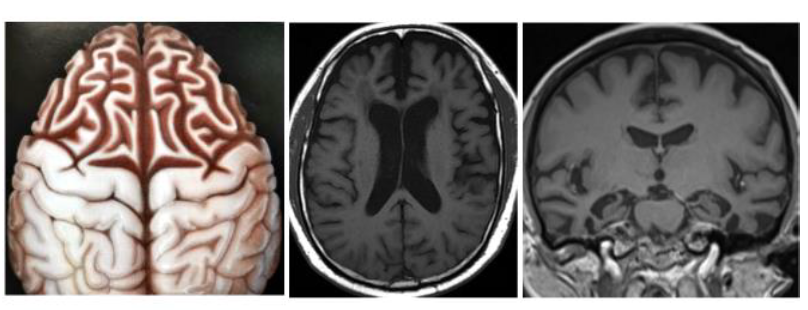

(3) 磁振造影術(MRI):既可直接看到全腦構造(圖四),又可看見阿茲海默症易損部位,如:海馬迴的萎縮及皮質變薄等(圖五)。可同時提供較完整的信息,所以成為目前失智症最重要的篩檢與診斷工具。

(圖四)正常人的大腦(左)與阿茲海默症病患的大腦(右),標識處為相異的特徵│資料來源:維基百科